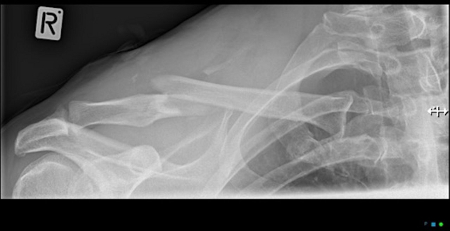

Clavicle fracture

Anteroposterior radiograph of right shoulder demonstrating clavicle fracture

Arnold S et al. BMJ Case Reports CP 2021;14:e241382; used with permission